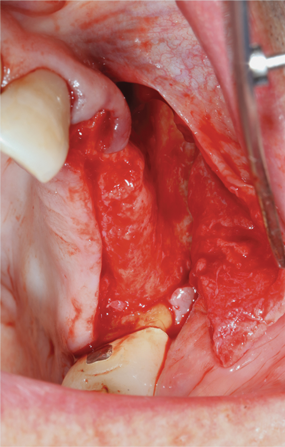

Fig 8. Incision design at maxillary left quadrant in preparation for lateral ridge augmentation.

Figure 8

Fig 9. Atrophic maxillary left quadrant ridge prior to ridge augmentation.

Figure 9